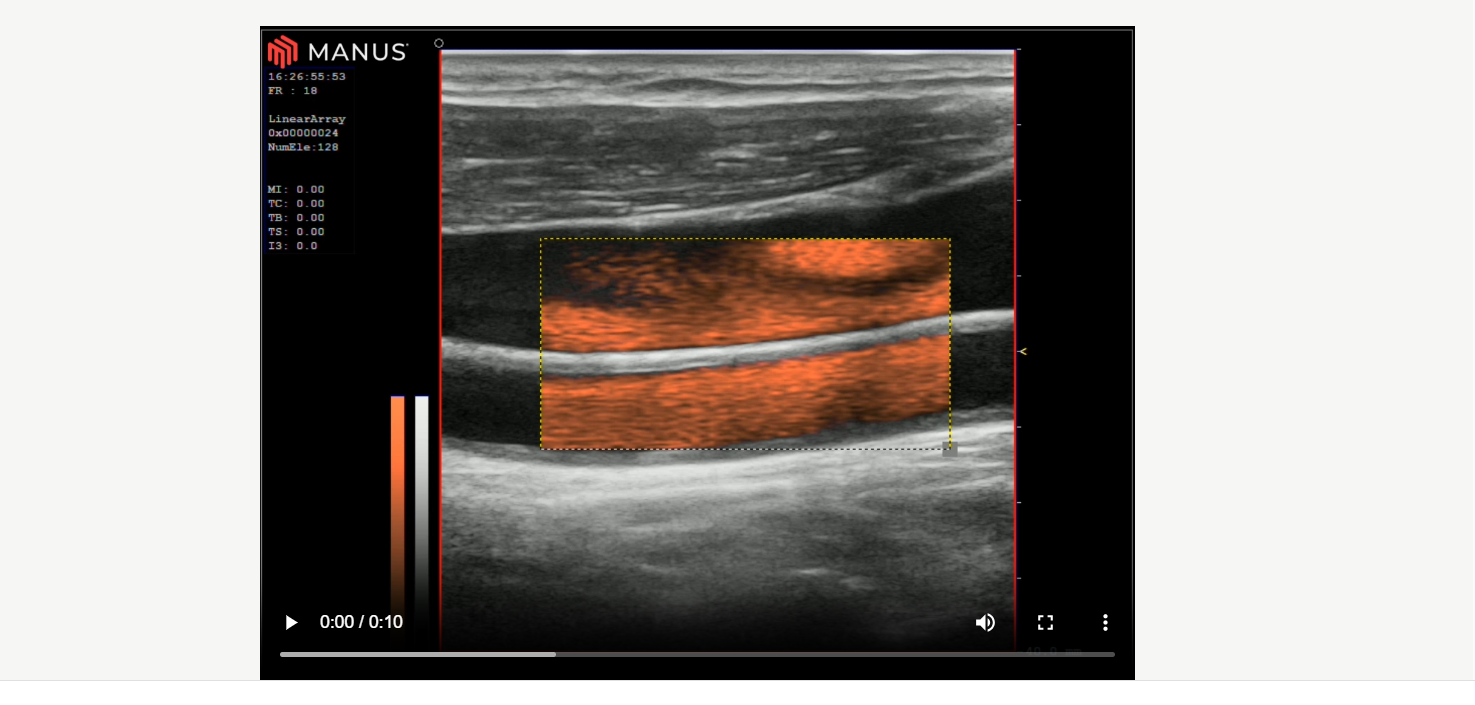

AUROTECH ultrasound are pleased to introduce our latest release, featuring new functionalities, updates, and performance improvements. For more details, please refer to the technical article. You can also watch video clips showcasing AFI (AUROTECH flow imaging).